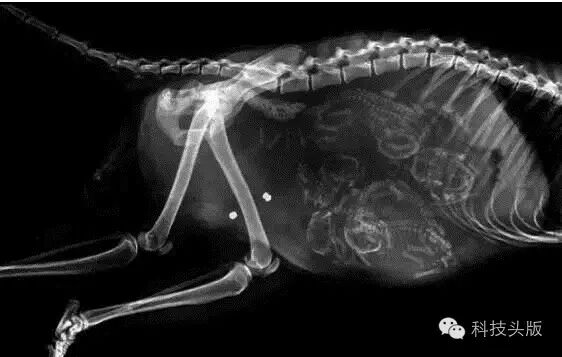

据称这是怀孕的虎鲨,另类而让人瞩目的存在。资料显示,虎鲨宝宝明明是卵生非胎生,那么图中这个一定是鲨鱼宝宝还在蛋壳里还没产出来的样子……